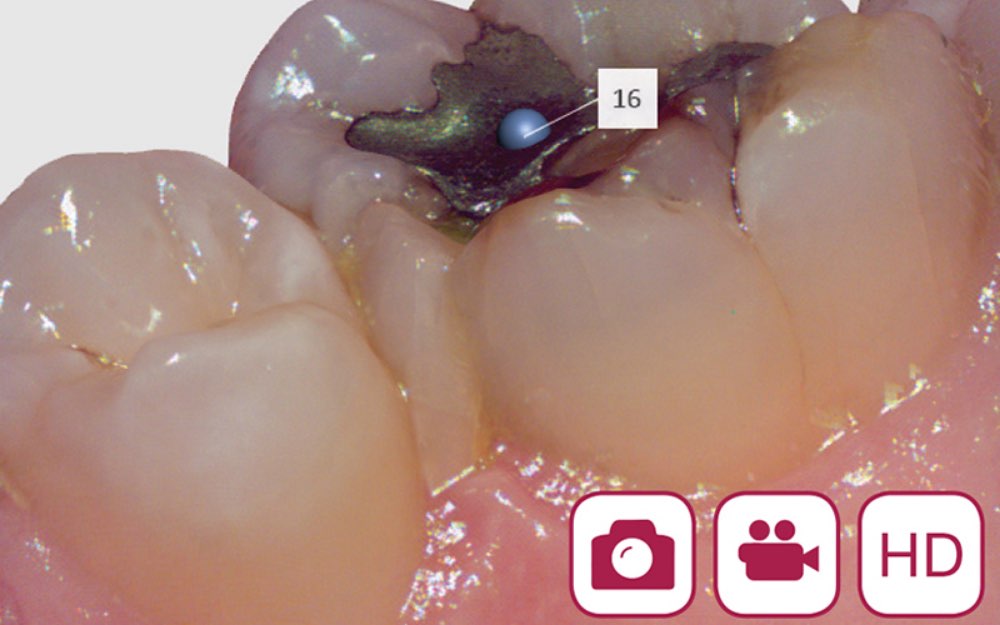

2|3D撮影によりリアルな光学印象が可能に

高解像度で撮影したデータを3Dでコンピューター上に表示することで、印象を採取した歯形よりも正確な光学印象を再現することができます。

4|動画と静止画による精密なデータ取得

高精細な画像や動画を撮影できるカメラが搭載されているため、小さなむし歯なども見逃さずに記録することができます。そのため、歯型をとる以外にも矯正などさまざまなシーンで使用します。